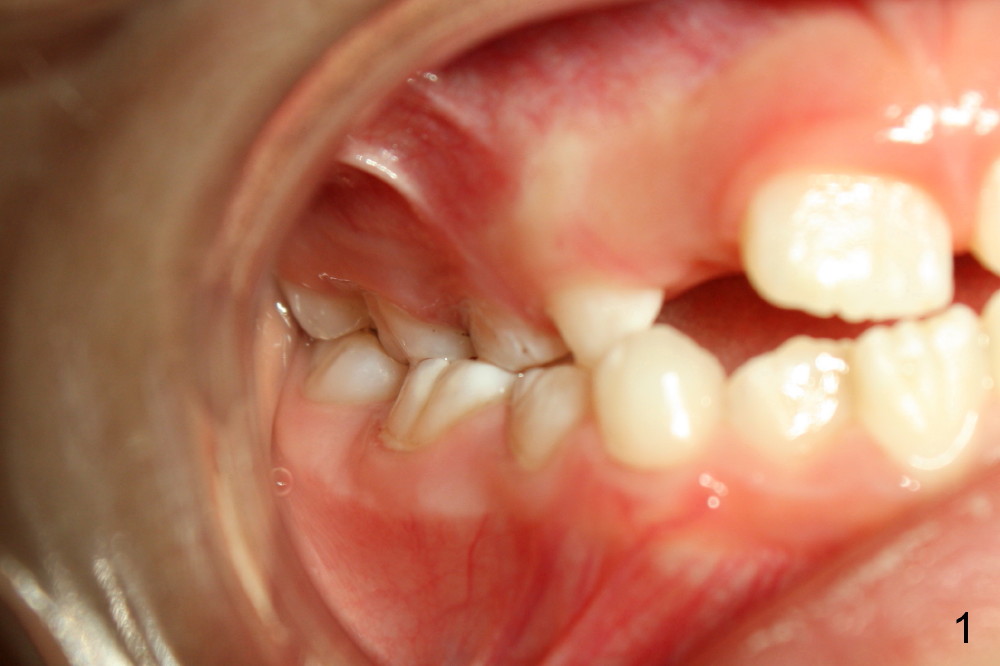

A 8-year-old girl presents malocclusion (Fig.1-3). What is the initial treatment?

Jenny: The girl has cross bite of both the anterior and posterior teeth. I think that first we need to expand her palate.